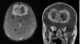

Intracranial tumor in a child